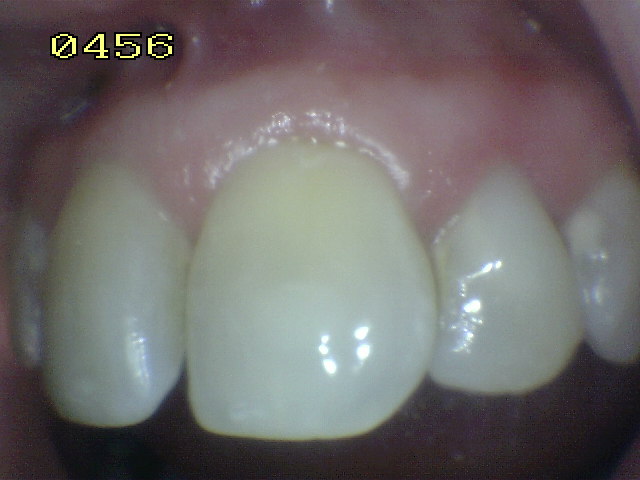

Tratamiento de hipoplasia del esmalte

en 21, semicarilla lumino-activada |

| Caso a tratar |